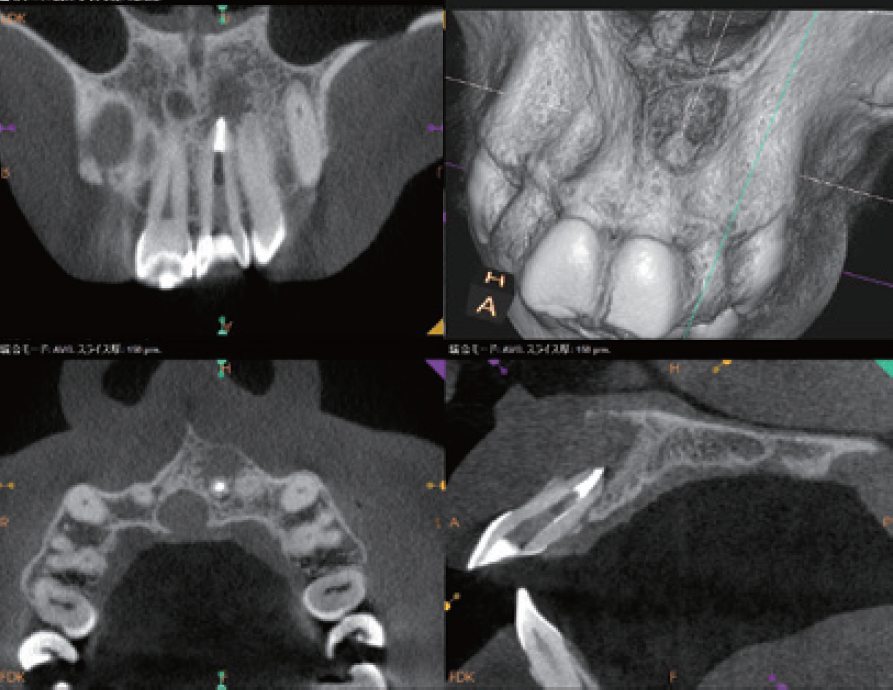

(症例1・①)根管充填の状態は比較的良好である。根管拡大・形成の3次元的評価のためCBCTを撮影。

CT像左上5番根尖部を中心として上顎洞粘膜の肥厚が認められ、根尖性歯周組織炎の影響が上顎洞まで及んでいると考えられた

根管処置後の修復が保存修復されて髄室開拡に制限があり、歯頸部周辺に存在する頬口蓋側に広がる髄角の形態が確認でき(症例1・②)、この部分に根管拡大不足の可能性を疑えた。根尖病変の原因として、頬口蓋的な根管拡大不足による起炎物質の取り残しによる感染が要因の一つであると診断した。より的確な予防形成を行うにあたり、器具操作の向上のため髄室開拡の修正が必要であると判断した。よって最終修復は歯冠修復による補綴修復が必要であると患者に説明し、承諾が得られたので再治療を行なった。

(症例1・②)

線で示した部分に髄角部の形態がそのまま残存していることが予測され拡大不足、未処置部分が存在すると判断した

(症例1・④)

術前と比較して頬口蓋方向に膨らんでいた髄角部の形態の変化が確認でき、未処置部分が減少していることが確認できる。上顎洞粘膜の肥厚も術前と比較し改善傾向にある

(症例1・⑤)根尖部のCBCT像

根尖部の開口部は3つ以上存在し、根管充填材が開口部を封鎖していることが確認できる